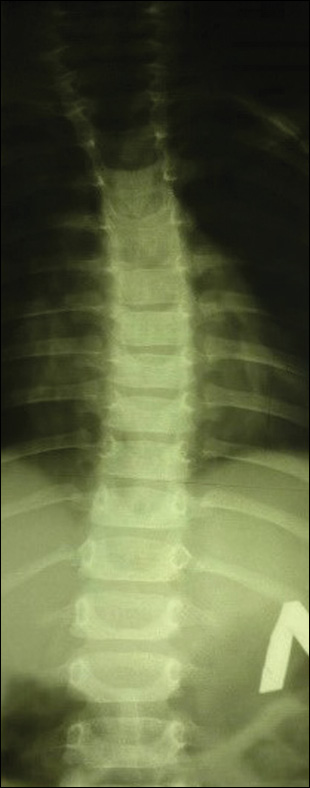

Пациент С., поступил в 14-е отделение вертебрологии НМИЦ ТО им. Н.Н. Приорова в возрасте 15 лет с жалобами на невозможность самостоятельной ходьбы и опоры на нижние конечности, деформацию позвоночника. Из анамнеза известно, что с двухлетнего возраста больной наблюдается у ортопеда по поводу сколиотической деформации грудного отдела позвоночника (рис. 6). В 13 лет впервые отметил неуверенность походки с эпизодами падения. В течение последующего года появились деформация стоп и прогрессирующая слабость в ногах. Пациент направлен на генетическое обследование. Выполнено секвенирование клинического экзома 6640 генов, выявлен вариант нуклеотидной последовательности в экзоне 11-го гена SH3TC2 в гетерозиготном состоянии. В экзоне 15-го гена SH3TC2 выявлен ранее не описанный вариант нуклеотидной последовательности в гетерозиготном состоянии, мутации в гене SH3TC2 расценены как патогенные. Данные мутации характерны для пациентов с болезнью Шарко–Мари–Тута, тип 4С. В анамнезе также выявлен синдром ночного апноэ с эпизодами снижения сатурации до SpO2=88%. По электронейромиографии нижних конечностей выявлено снижение скорости проведения по нервам ниже 22 м/с.

Рис. 6. Постуральная рентгенография позвоночника в возрасте двух лет жизни.

Fig. 6. Postural radiography of the spine at two years of age.

По данным постуральной рентгенографии позвоночника в двух проекциях: картина левостороннего кифосколиоза грудного отдела позвоночника IV степени, угол Cobb сколиотической дуги 90° с вершиной Th6–7, угол кифотической дуги 115° с вершиной Th6–7 (рис. 7).

Рис. 7. Постуральная рентгенография позвоночника на момент поступления.

Fig. 7. Postural radiography of the spine at the time of admission to hospital